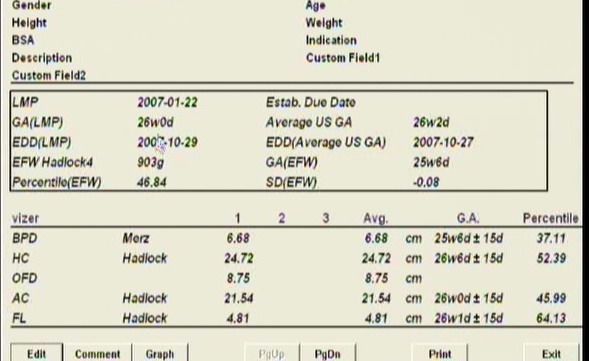

Pénteken voltunk 4D-n, nagyon édes pofis képet kaptunk, de csak aug. 6. után tudom feltenni. És képzeljétek, majdnem 2 héttel nagyobb a koránál, 1030 gr-ot becsületek, meg is ijedtem rendesen, hogyan fogom megszülni! Még tokája is van